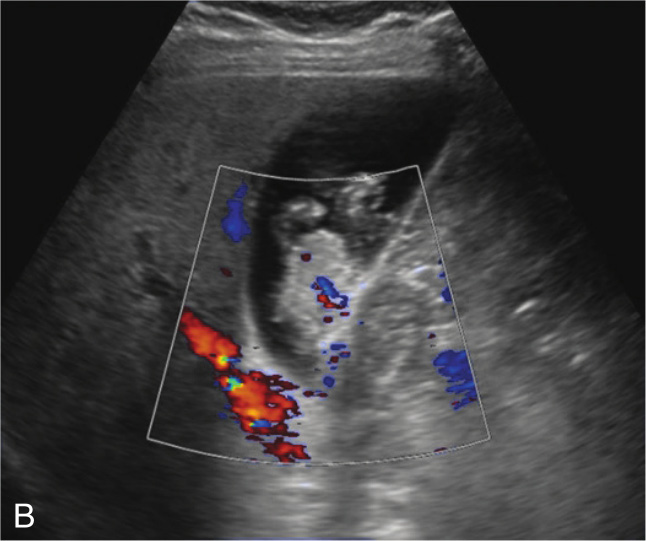

图2-5-2(续)

B.局部放大图像显示增厚处胆囊壁不光滑、形态不规则(箭头所示)